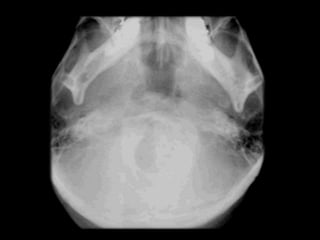

 skull base and condyle

 Angulation of long axis of condylar head

 Provides a view of T.M.J. in lateral plane

 evaluating

▪ Displaced Condyles

▪ Rotation Of Horizontal Plane Associated With Trauma Or Facial

Asymmetry

Tracing of angles between the long axis of each condyle and the midsagittal plane.

For tomography views the patient is rotated according to the measured angles to

produce an undistorted radiographic view of each T.M.J.

 To investigate the Articular surface of the

condyles and disease within the joint

 Fractures of the condylar heads and necks

 Patient is positioned facing the film

 Head tipped downward

 Forehead and nose touching the cassette

 X ray tube is aimed upward at 30⁰ from behind

 Used for screening purposes

 Both condyles can be visualized

 Gross osseous changes can be identified

 Disadvantage of superimposition